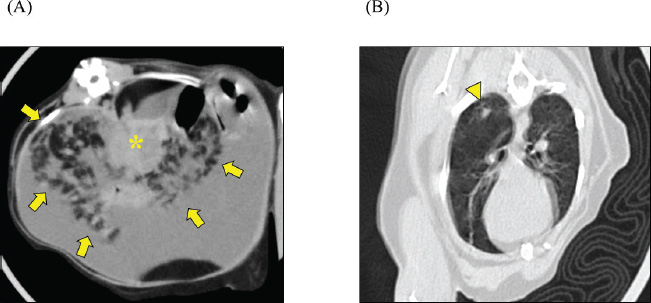

A 2-year-old castrated male domestic shorthair cat, weighing 5.3 kg, presented with a 2-month history of abdominal distension and a 4-day history of anorexia. There was no history of illness or abdominal surgery. Physical examination revealed severe abdominal distension with a fluid wave and mild hypothermia (37.1°C). Blood tests revealed mild elevations in blood glucose (178 mg/dl; reference interval 71–148 mg/dl) and serum amyloid A (5.27 µg/ml; reference interval <3.75 µg/ml) levels, while lipase activity was within normal limits (23.9 U/l; reference interval <30 U/l). Abdominal radiography revealed increased radiopacity and digestive tract consolidation (Fig. 1). Abdominal ultrasonography revealed severe ascites, small intestine hypoperistalsis, pancreatic enlargement, and irregular thickening of the peritoneum with several nodules (Fig. 2). Echocardiography revealed no abnormality. In the ascitic fluid analysis, the total nucleated cell count was 1,000 cells/μl with no evidence of neoplastic cells or bacterial infection, and the specific gravity of the supernatant was 1.024, confirming the ascites as a modified transudate (Fig. 3). Feline infectious peritonitis was considered unlikely due to the absence of feline coronavirus genes in the ascitic fluid and no elevation in blood anti-coronavirus antibody titers. Based on the imaging findings, such as peritoneal thickening, gastrointestinal tract consolidation, and severe ascites, EPS was initially suspected. These findings are consistent with the typical presentation of EPS, characterized by fibrotic thickening of the peritoneum and encasement of abdominal organs (Gremillet et al., 2022). However, the possibility of malignancy was deemed unlikely due to the cat’s relatively young age. A trial treatment with prednisolone (10 mg/head, q24 h) and enrofloxacin (25 mg/head, q24 h) was initiated to manage the suspected inflammatory process and potential bacterial infection, respectively. However, no clinical improvement was observed, suggesting that the underlying condition might be more complex than initially suspected. A non-sedated computed tomography (CT) scan was performed to obtain more detailed diagnostic information on day 12 after presentation. A Siwtenn-slice multi-slice CT scanner (Aquilion™ Lightning, Canon Medical Systems, Japan) was used without anesthesia, with the patient restrained in an acrylic cage (CT capsule, Terucom, Japan). The following technical parameters were used: rotation time=0.75 s; slice thickness=1 mm; reconstruction interval=0.5 mm; table speed=16 mm/rotation; helical pitch=16.0; X-ray tube voltage=120 kV; and X-ray tube current=100 mA. The CT scan revealed a tumor-like enlargement of the pancreas, irregular scattered nodular formations aggregating dorsally in the peritoneum, and ground-glass opacity in the right lower lobe of the lung (Fig. 4). Because angiography was not performed, the vascular characteristics and more detailed differentiation of the soft tissue masses could not be assessed. A pancreatic tumor was suspected; however, diagnostic and therapeutic surgical interventions were deemed difficult due to the animal’s condition. In addition, the owner declined further invasive procedures, such as fine-needle aspiration or laparoscopy. Despite prednisolone treatment (5 mg/head, 24 h), ascitic fluid drainage, and fluid therapy, the cat died 19 days after the first presentation.

Fig. 4. CT scan. Transverse CT images of (A) upper abdomen and (B) chest are shown. The mesenteric fat exhibited scattered nodules with irregular contours (arrow) centered around the enlarged and tumorous pancreas (*). Ground-glass opacity was observed in the right lower lobe of the lung (arrowhead).